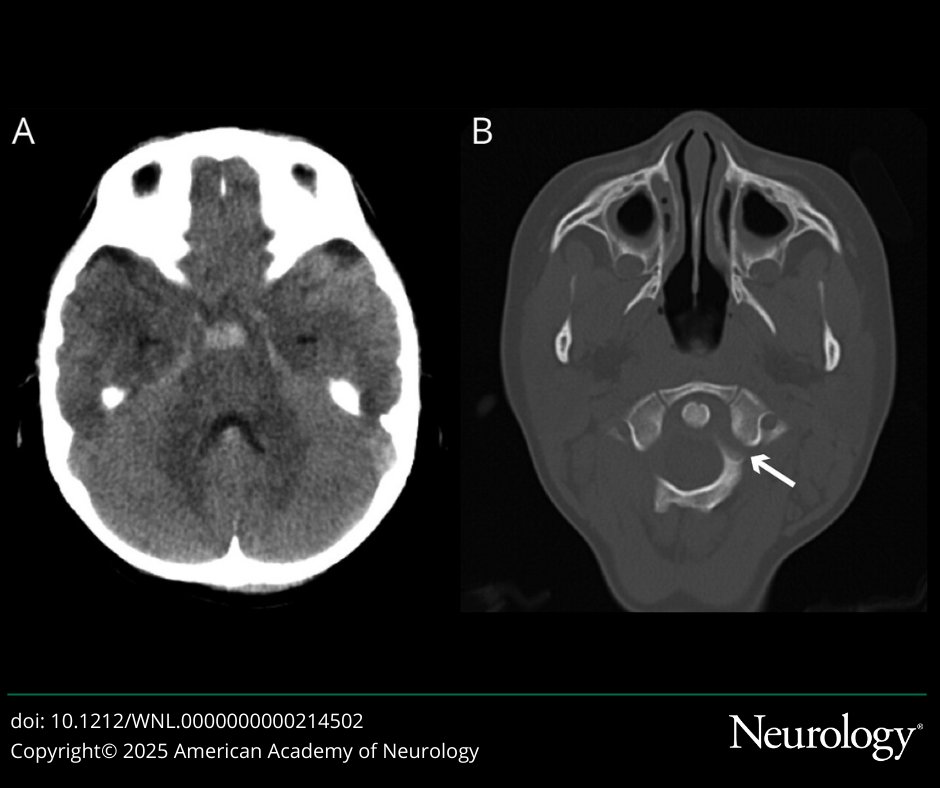

This Video #NeuroImage depicts traumatic atlantoaxial rotatory fixation in a young child (video at link): https://t.co/Jq19vcqIG1